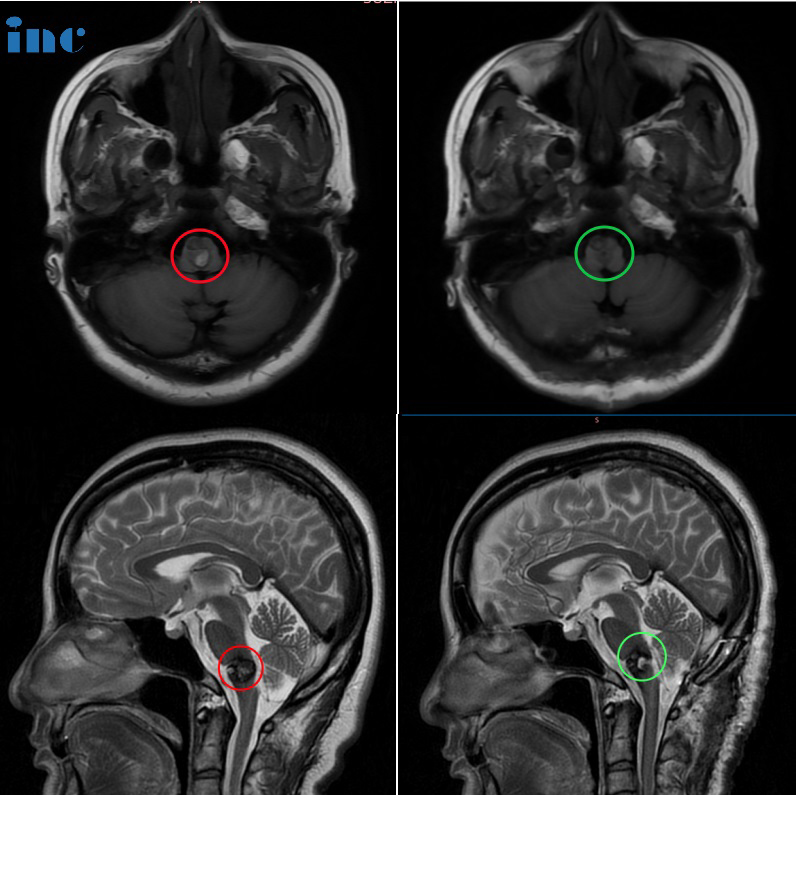

38岁男性-脑干(桥臂)海绵状血管瘤

病史摘要:卢先生的求医之路坎坷,三度脑干出血,甚至被送进ICU,但是“就诊了挺多医院,但是到医院去,各大医院的教授都说这个手术风险太大,建议我保守治疗,我也没办法,我该怎么办?”病情也只能一拖再拖。,这台成功示范教学手术帮助他完全摆脱了病魔的困扰。

▼脑干海绵状血管瘤术前MRI

治疗过程:在苏州独墅湖医院,巴教授为他顺利全切脑干海绵状血管瘤。

术后情况:手术当天,等候在手术室外的卢先生爱人焦急得询问着手术结果。看到巴教授的一句话就是:“很顺利吗?”当听到教授坚定的回复:“很顺利!”她露出了久违的笑容,激动的拥抱巴教授,“感谢,感谢!”为了让家属了解到患者的手术情况,巴教授甚至用中文说:“全切”。听到这样的好消息,卢先生爱人再次表达谢意:“Very good!谢谢!”术后1天转出ICU,转入普通病房,术前担心的面瘫也都没有发生。

28岁女性-脑干海绵状血管瘤

病史摘要:28岁的琳琳罹患脑干海绵状血管瘤,从2023年9月底至今,短短不到2个月时间,已经出过2次血,但是医生给出的评估都是手术风险较大。

▼2023年9月琳琳核磁影像

▼2023年11月头颅CT

2023年9月底,一开始出血

症状:复视(看1米起及远处)、左眼外展受限,易疲惫,嗜睡,手掌微麻。诊断为海绵状血管瘤。

2023年11月初,二次出血

症状:复视和右手脚掌麻,和之前一开始相比,眼部症状明显严重一些,易疲惫,嗜睡。

医生判断脑干海绵状瘤二次出血,对比一开始出血量增多。医生建议手术并告知术后可能出现偏瘫、呼吸障碍等神经功能损伤。

治疗过程:北京时间2023年11月21日,由INC国际神经外科顾问团成员、国际神经外科联合会(WFNS)教育与技术委员会前主席Helmut Bertalanffy(巴特朗菲)教授主刀,中国神经外科专家密切配合之下,一例高难度脑干延髓海绵状血管瘤全切手术在苏州大学附属独墅湖医院顺利完成。术后,患者状态良好,没有新发功能障碍,术前症状也在逐渐恢复。

术后情况:“All removed?So great!Thank you,Professor”,术后1天,当听到巴教授说脑干部位的海绵状血管瘤得到了全切,且今天就可以转出ICU,转入普通病房时。一直陪同琳琳的家人们激动之情溢于言表,心中的石头总算落了地。同时,他们也对这位人称“巴教授”的德国专家充满了敬佩和感激。